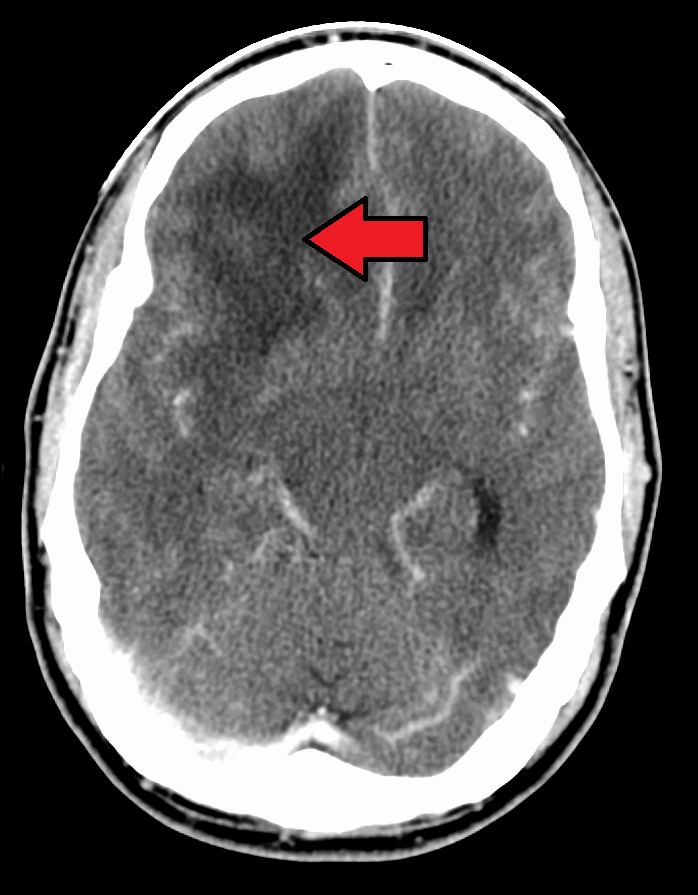

; MRI

: T1 강조 영상에서는 종양이 약간 저신호역, T2 강조 영상에서는 종양과 그 주변의 뇌부종이 고신호역이 된다. 가돌리늄을 사용한 조영 MRI에서는 종양의 변연이 고신호역이 되는 한편, 종양 내부는 괴사 등을 반영하여 저~고신호역이 뒤섞인 영상이 되는 경우가 많다. 이 소견을 링 강화라고 칭한다. 또한, 링 강화는 교모세포종에 특이적인 소견이 아니며, 뇌농양, 전이성 뇌종양 등이 감별로서 거론되는 경우가 많다.

- MRI: T1 강조 영상에서는 종양이 약간 저신호역, T2 강조 영상에서는 종양과 그 주변의 뇌부종이 고신호역이 된다. 가돌리늄을 사용한 조영 MRI에서는 종양의 변연이 고신호역이 되는 한편, 종양 내부는 괴사 등을 반영하여 저~고신호역이 뒤섞인 영상이 되는 경우가 많다. 이 소견을 링 강화라고 칭한다. 또한, 링 강화는 교모세포종에 특이적인 소견이 아니며, 뇌농양, 전이성 뇌종양 등이 감별로서 거론되는 경우가 많다.

- MRI: T1 강조 영상에서는 종양이 약간 저신호역, T2 강조 영상에서는 종양과 그 주변의 뇌부종이 고신호역이 된다. 가돌리늄을 사용한 조영 MRI에서는 종양의 변연이 고신호역이 되는 한편, 종양 내부는 괴사 등을 반영하여 저~고신호역이 뒤섞인 영상이 되는 경우가 많다. 이 소견을 링 강화라고 칭한다. 링 강화는 교모세포종에 특이적인 소견이 아니며, 뇌농양, 전이성 뇌종양 등이 감별로서 거론되는 경우가 많다.